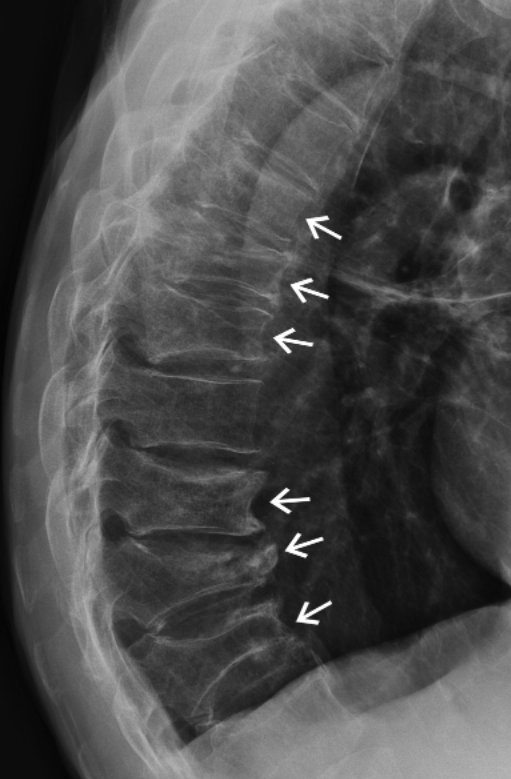

What does this X-ray show?

A vertebral fracture cascade